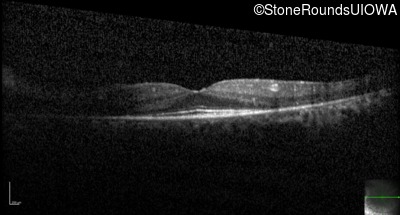

Optical Coherence Tomography - Right - 20/25

Exemplar / OCT Stack

Optical Coherence Tomography - Left - 20/32 -1

Optical Coherence Tomography - Left - 20/25

Optical Coherence Tomography - Right - 20/30 -1

Optical Coherence Tomography - Left - 20/30